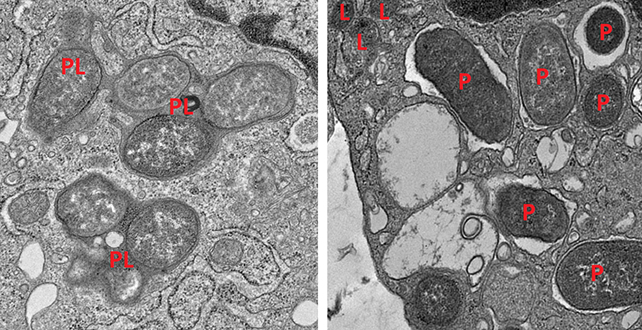

Macrophages in the gut can switch between two states, one for attacking infection (inflammatory) and one for repairing damage (non-inflammatory). It’s been well established that keeping these two states balanced is important for a healthy gut.

One gene found to promote the non-inflammatory macrophage mode produces a protein called girdin. It turns out that the girdin and NOD2 proteins work together to ensure macrophages remain alert to threats, but not overly reactive. Without them, macrophages in repair mode are less efficient at cleaning up targets, while those in attack mode are overly inflammatory.